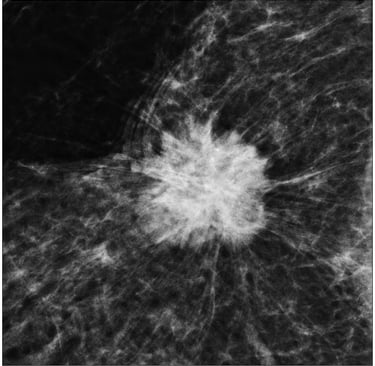

Mikrokalsifikasyonlar: LR (+) 15.0. (Özellikle pleomorfik/dallanan tipteyse)

Spiküle Kitle: LR (+) > 20.0.

"Mamografide Spiküle (Dikenli) Kitle Varlığı ile Luminal A Alt Tip Meme Kanseri Arasında Bir Korelasyon Var mıdır?"

Bu çalışma, mamografik görüntüleme bulguları ile meme kanserinin moleküler alt tipleri arasındaki biyolojik bağı incelemektedir. 317 hastanın retrospektif analizi üzerinden yapılan çalışma, fenotip (görüntü) ile genotip (moleküler belirteçler) arasındaki ilişkiyi Bayesyen bir olasılık çerçevesinde sunar.

1. Temel Bulgular ve İstatistiksel Veriler

Luminal A Dominansı: Spiküle (kenarları ışınsal uzantılı) kitlelerin %71'i Luminal A alt tipi olarak sınıflandırılmıştır.

Olasılık Oranı (Odds Ratio): Luminal A alt tipindeki kitlelerin, diğer alt tiplere oranla mamografide spiküle görünüm sergileme olasılığı 10.3 kat daha fazladır (p < 0.001).

Biyobelirteç Korelasyonu: Spiküle görünümün en güçlü öngörücüleri Düşük Ki67 indeksi (< %14) ve HER2 negatifliğidir. Hormon reseptör (ER/PR) pozitifliği de ilişkili bulunmuştur ancak etkisi Ki67 ve HER2 kadar baskın değildir.

2. Klinik ve Prognostik Çıkarımlar

İyi Prognoz İşareti: Spiküle marjlar, genellikle tümör hücrelerinin çevre dokuyla (stroma/yağ dokusu) etkileşimini ve düşük dereceli (low-grade) progresyonu gösterir. Bu durum, spiküle kitlelerin neden daha iyi bir prognoza işaret ettiğini açıklar.

Tanısal Doğrulama: Eğer bir tümör mamografide spiküle görünüyorsa ancak patolojide "HER2 pozitif" geliyorsa, bu bir uyumsuzluk (discordance) bayrağıdır; testin tekrarı düşünülebilir.

3. Sonuç

Mamografide görülen spiküle kitle, invaziv meme kanserinin Luminal A alt tipi için güçlü bir radyolojik belirteçtir. Bu korelasyonun temelinde tümörün düşük proliferatif aktivitesi (Ki67) ve HER2 gen ekspresyonunun olmaması yatar. Bu veriler, "spiküle kitle" verisinin, biyopsi öncesi Luminal A olasılığını (prior probability) belirgin şekilde yükselttiğini kanıtlamaktadır.